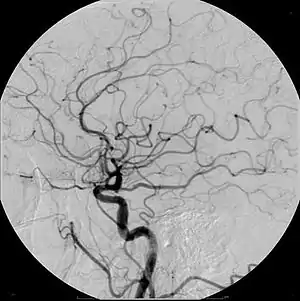

Example of iodine-based contrast in cerebral angiography

In order to remove the distracting structures to see the vessels better, first a mask image is acquired. The mask image is simply an image of the same area before the contrast is administered. The radiological equipment used to capture this is usually an X-ray image intensifier, which then keeps producing images of the same area at a set rate (1 to 7.5 frames per second). Each subsequent image gets the original "mask" image subtracted out. (Mathematically, the incoming image is divided by the mask image.) The radiologist controls how much contrast media is injected and for how long. Smaller structures require less contrast to fill the vessel than others. Images produced appear with a very pale grey background, which produces a high contrast to the blood vessels, which appear a very dark grey.[4]

DSA is primarily used to image blood vessels. It is useful in the diagnosis and treatment of arterial and venous occlusions, including carotid artery stenosis, pulmonary embolisms, and acute limb ischaemia; arterial stenosis, which is particularly useful for potential kidney donors in detecting renal artery stenosis (DSA is the gold standard investigation for renal artery stenosis[9]); cerebral aneurysms and arteriovenous malformations (AVM).